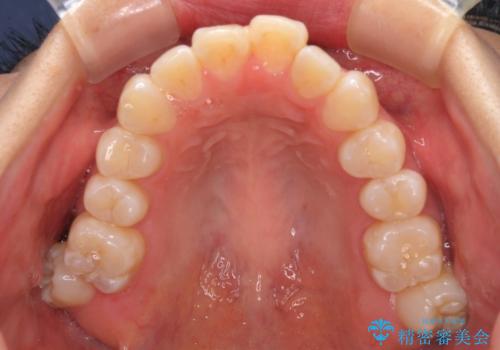

外に飛び出して磨きにくい奥歯と上下前歯の隙間 インビザラインによる矯正治療

- 上下前歯の隙間と、外側を向いていて歯磨きのしにくい奥歯を気にして来院された患者様です。

下顎前歯が1本欠損しており、上下アーチはアンバランスとなりますが、インビザラインを用いて上下の隙間を改善しながら歯列を整えることとしました。

外側を向いている奥歯は、内側にアンカースクリューを埋入して牽引の固定ゲント氏、部分的にワイヤー装置を用いることで歯列に納めることとしました。

下顎前歯の1本欠損により左右の咬合が不安定となり、治療経過で噛みにくい状態が続きましたが、最終的には違和感なく噛めるようになりました。